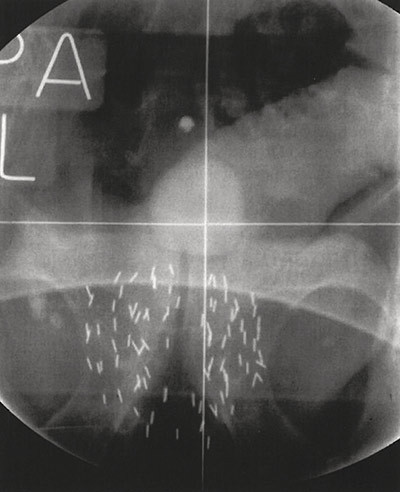

Figure 2  Radiological scan of the pelvis after low-dose-rate brachytherapy. Multiple radioactive iodine seeds are implanted…

Figure 2 Radiological scan of the pelvis after low-dose-rate brachytherapy. Multiple radioactive iodine seeds are implanted permanently in the prostate gland. The patient is catheterised and the balloon in the bladder above the symphysis is clearly visible. Photo: Bereich Interdisziplinäre Brachytherapie, Universitätsklinikum Schleswig-Holstein, Campus Lübeck. Published with the permission of Dr György Kovács